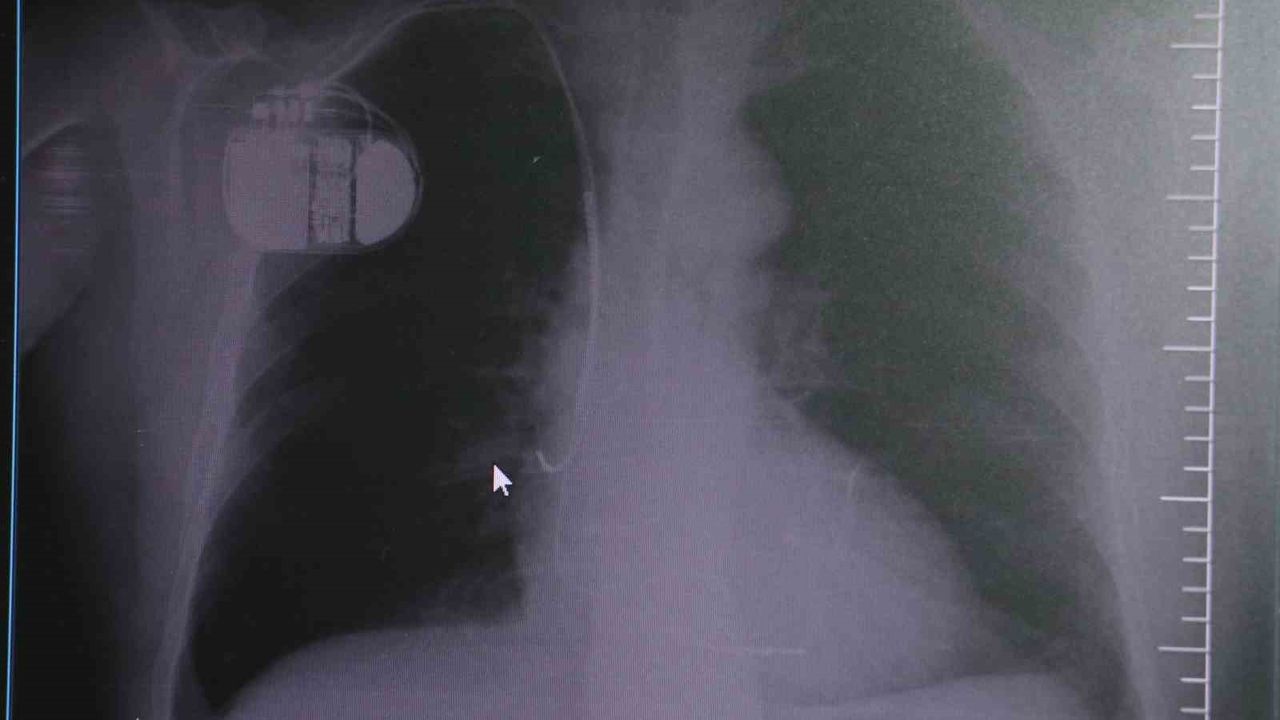

Kalp krizleri sonrası kalp dokusunun zarar gördüğünü söyleyen İsmail Erdoğu, "Dünyada artık kalp hastalıkları en sık ölüm sebeplerinden biri. Kalp hastalıklarında çok fazla grup var. Biz kalp hastalıkları deyince sadece kalbinde stent olan ve damarlarında sorun bulunan insanlardan bahsetmiyoruz. Aynı zamanda tansiyon ve şeker hastaları da kalp hastalıklarına aday. Toplumun yaklaşık yüzde 30-35’lik bir kısmını kapsıyoruz. Çok yaygın bir hastalık ve bu hastalıkta teknolojik kapsamda, ilaç konusunda son 30 yılda çok ciddi gelişmeler oldu. Geçmişte insanları hastanelerde kalp krizinden dolayı kaybederken şimdi hastaneye başvurular sonrasında yaşama tutunmak büyük oranda mümkün. Yaşanan ölümler ise genellikle hastaneye gelmeden önce gerçekleşmekte. Kalp krizinden kurtulmanın hastalarda belli bir bedeli oluyor. Kalp krizi sonrası kalpteki dokular zarar görüyor ve kalp yetersizliği oluşuyor. Bu kalp yetersizliği olan kalplerde ritim bozuklukları ve ani ölümler gibi sorunlar gündeme gelebiliyor. Bunlardan uzun vadede korunmak için hastalarda mutlaka bir kalp piline ihtiyaç duyuluyor" dedi.

Kalp pilleri ile MR cihazına girilebileceğini belirten Erdoğu, "Çok büyük bir ameliyat değil ama yine de ciddi bir cerrahi işlem. Kalp pili, tıpta son 30 yılda yaşanan gelişmelerden en büyüğü. Bir bilgisayarın küçültülüp insan vücuduna konulmuş hali aslında. İnsan ömrünü ciddi oranda uzatan bir tedavi. İnsanlar bir şokla hayata tutunurken, pil olmasaydı öleceğini düşündüğümüz birçok hastamız var. Kalp pilinin bu özelliği, uygun hastalarda ciddi oranda ani ölümü engelliyor. Hastanın başına gelecek bir kalp durması durumunda yanında bir sağlıkçı yoksa, onun ritmini düzeltecek defibrilatör cihazı yoksa hastayı hayatta tutmak mümkün değil. Uygun endikasyonlarda kalp pili olduğu zaman, pil hastaların ritmini algılıyor ve acilde yapılan şoklamayı yaparak hastayı hayata döndürüyor. Kalp pillerinde yeni teknolojilerle MR’a girmek mümkün, tomografiye zaten girebiliyorlar. Tarama cihazlarından geçmelerini uygun görmüyoruz. Bu tarz durumlarda hastalarımız ’kalp pilim var’ dediğinde muaf tutuluyorlar. Kalp pilleri ciddi teknolojik cihazlardır. Vücudun içindeki titreşimi, örneğin mikser kullanmak, kolunu sallayacak herhangi bir eylem kalp pilinde olumsuz etki oluşturabilir. Soğuk havalarda vücutta oluşan ciddi titremeler kalp pilinin hafızasını karıştırıp kalbin durduğunu düşündürebilir ve gereksiz şoklama yapabilir. Bu tarz kişilerin soğuk havalarda daha temkinli olması gerekir" diye konuştu.